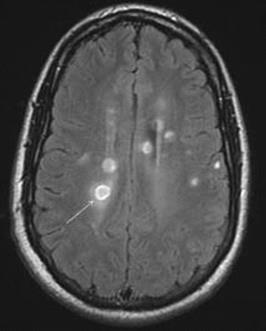

Figure 22.1 Axial FLAIR MRI showing characteristic T2-hyperintense plaques (arrows) in a patient with MS.

demonstrating CNS demyelination separated in both space and time, and MRI is capable of offering important information in both dimensions. Standard MS protocols should include T1, T2, fluid attenuation inversion recovery (FLAIR; in both the axial and sagittal planes), and contrast-enhanced T1 images of the brain. Patients with spinal presentations require T1, T2, and contrast-enhanced T1 images of the spine. A diagnosis of MS is highly unusual when multiple imaging studies are normal.

T2 and fluid attenuation inversion recovery imaging

The T2 hyperintense plaque is the characteristic MRI finding of demyelination secondary to MS (Figure 22.1). Plaques are generally easier to visualize by FLAIR, a sequence in which the bright CSF signal is removed. Common plaque locations are in the periventricular white matter, corpus callosum, centrum semiovale, and middle cerebellar peduncle. Although plaques may have a variety of appearances, those that are ovoid in shape are most suggestive of MS. Lesions in the corpus callosum that are oriented perpendicularly to the lateral ventricles are known as Dawson’s fingers (Figure 22.2) and are particularly characteristic of MS. These lesions are best visualized using FLAIR sequences in the sagittal plane. Plaques may accompany both new and old (presumably inactive) MS symptoms.